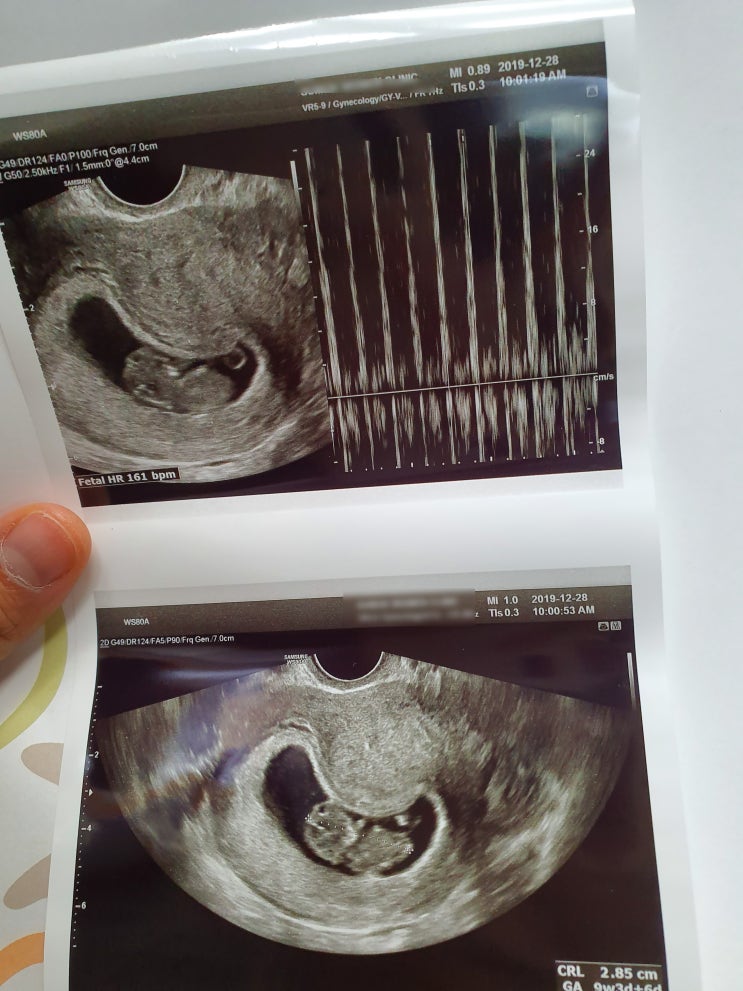

[임신8주-12주] 1차기형아검사,입체초음파,산부인과변경,산후조리원예약

하잉하잉 점점 게으름의 끝을 달리고 있는 저입니다 왜이리 꼼짝도 하기 싫은지 .. 큰일이네요 ㅠㅠ 입덧은...